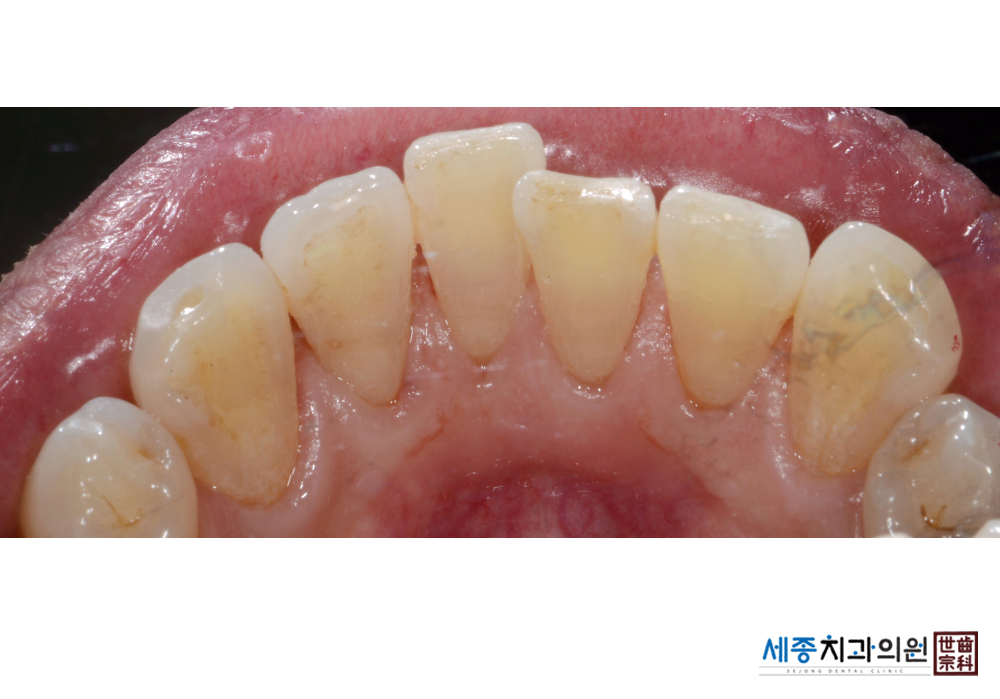

[스케일링] 치주질환 예방 스케일링

치료전 : 2020-01-16

치료후 : 2020-01-16

가글마취&저주파 스켈러를 사용한 스케일링